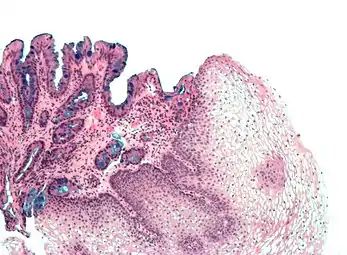

| Tinción hematoxilina-eosina | Bicomponente Anfifílica |

Tinción histológica general | ![]() |